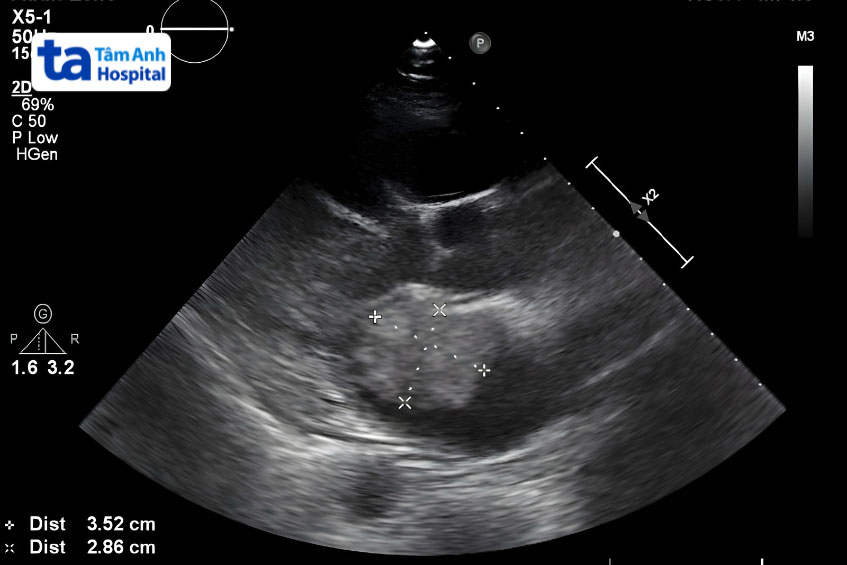

Việc chẩn đoán u nhầy có thể gặp một số khó khăn do triệu chứng của bệnh thường giống với nhiều bệnh lý tim mạch khác. Để chẩn đoán chính xác khối u này, bác sĩ thường thực hiện một số phương pháp như:

Sau khi hoàn thành các bước thăm khám lâm sàng, bác sĩ sẽ thực hiện kết hợp một số kỹ thuật chẩn đoán hình ảnh chuyên sâu hơn, chẳng hạn như: